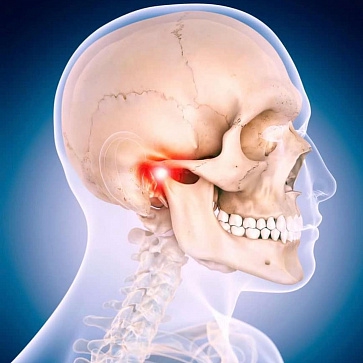

Аноним 20/10/25 Пнд 10:21:34 1645654 31

image.png 421Кб, 512x370

512x370

Парни, может посоветуйте что. Ходил к терапевту с проблемой с шеей, а именно чувства онемения с левой стороны, при повороте шеи влево. У меня нашли остеохондроз первого левела и прописали какие то таблетки, которые нигде у нас не продают, посоветовали делать упражнения для шеи, НО после того как я начал заниматься, то мне стало постепенно очень хуево: головная боль, которая шла от шеи, сама шея начала ныть и постоянно хрустеть при поворотах, начала немного неметь нога. Перестал делать упражнения и всё стало снова нормально.

ПОэтому вопрос, почему от упражнений хуже? Я вроде всё медленно делаю, разминаюсь

Второй вопрос, что с моей шеей по итогу? Всё началось, когда я проснулся и я почувствовал какое то инородное тело где показано на пике, потом это чувство прошло, но перешло в онемение с левой стороны шеи. Терапевт ничего не нащупал, сказал просто защемило чо то, делай упражнения и пройдет

Аноним 20/10/25 Пнд 13:48:24 1645685 38

>>1645682

Не, у меня тема с онемением началась ДО лфк. Как раз я начал делать лфк из за этой проблемы по совету терапевта. А фото вообще не мое, просто для понимания кинул